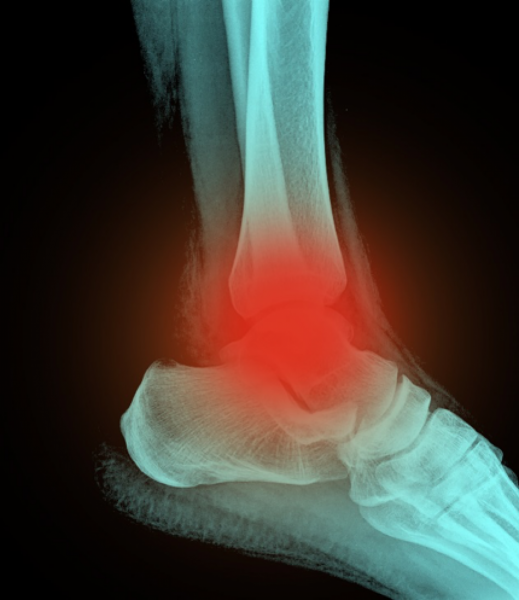

Leg, Knee and Ankle Pain

Common causes of leg, knee and ankle pain include:

• Referred pain from an irritated nerve in the spine.

• A vertebral disc injury such as a slipped disc or trapped nerve

• Referred pain from low back, hip or pelvis.

• Sprained joint or ligament.

• Tendonitis. Commonly from repetitive use of a joint or muscle causing inflammation in the tendons.

• Degeneration of a joint.

• Muscle strain. Injuries sustained from physical activity maybe more complicated than it initially seems.